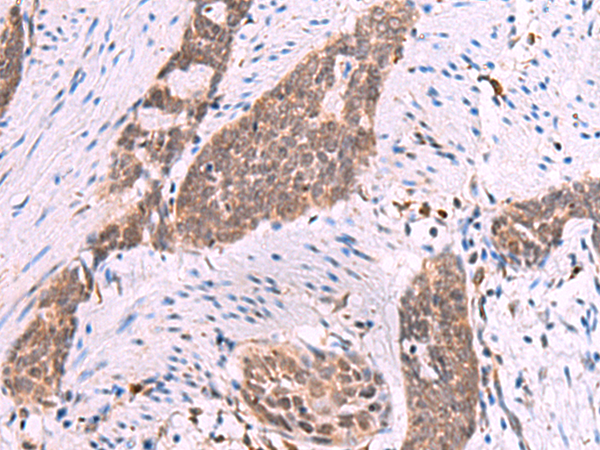

IHC positive control: |

Human thyroid cancer and Human esophagus cancer |